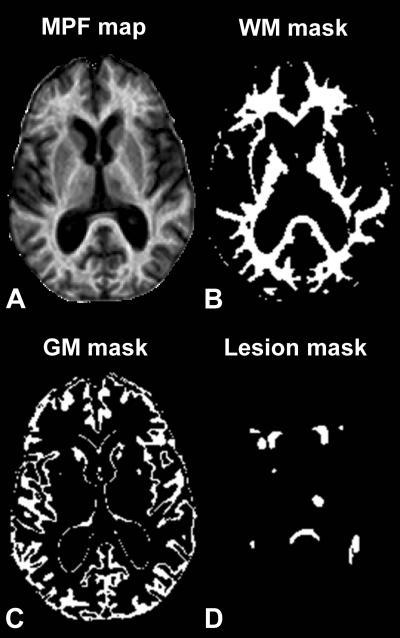

These are example axial sections of a three-dimensional MPF map (A) obtained from a 63-year old woman with SPMS disease course and results of brain tissue segmentation (B-D). Segmentation masks corresponding to white matter (WM) (B), gray matter (GM) (C), and lesions (D) were used to calculate mean MPF values in each tissue.

(Photo Credit: Radiological Society of North America)